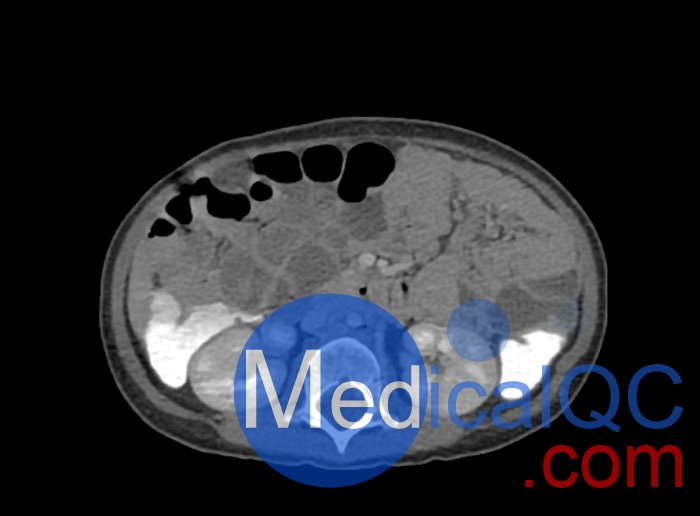

WEK58-03兒童軀干模型,WEK58-03兒童軀干模體模擬了 1 歲兒童的造影劑增強了門靜脈期的胸部、腹部和骨盆。它覆蓋了會陰的第六頸椎。結(jié)腸充滿造影劑,如直腸給藥后。

WEK58-03兒童軀干模型,WEK58-03兒童軀干模體提供了對軟組織和骨組織的詳細(xì)而逼真的模擬。包括肺在內(nèi)的空隙充滿了大約 -160HU的纖維素聚合物復(fù)合材料。

真實模擬脈管系統(tǒng)、骨骼和軟組織,包括肺、心臟、肝臟、膽囊、胰腺、脾臟、腎上腺、腎臟、胃、小腸、結(jié)腸和膀胱。

WEK58-03兒童軀干模型,WEK58-03兒童軀干模體成像效果圖: